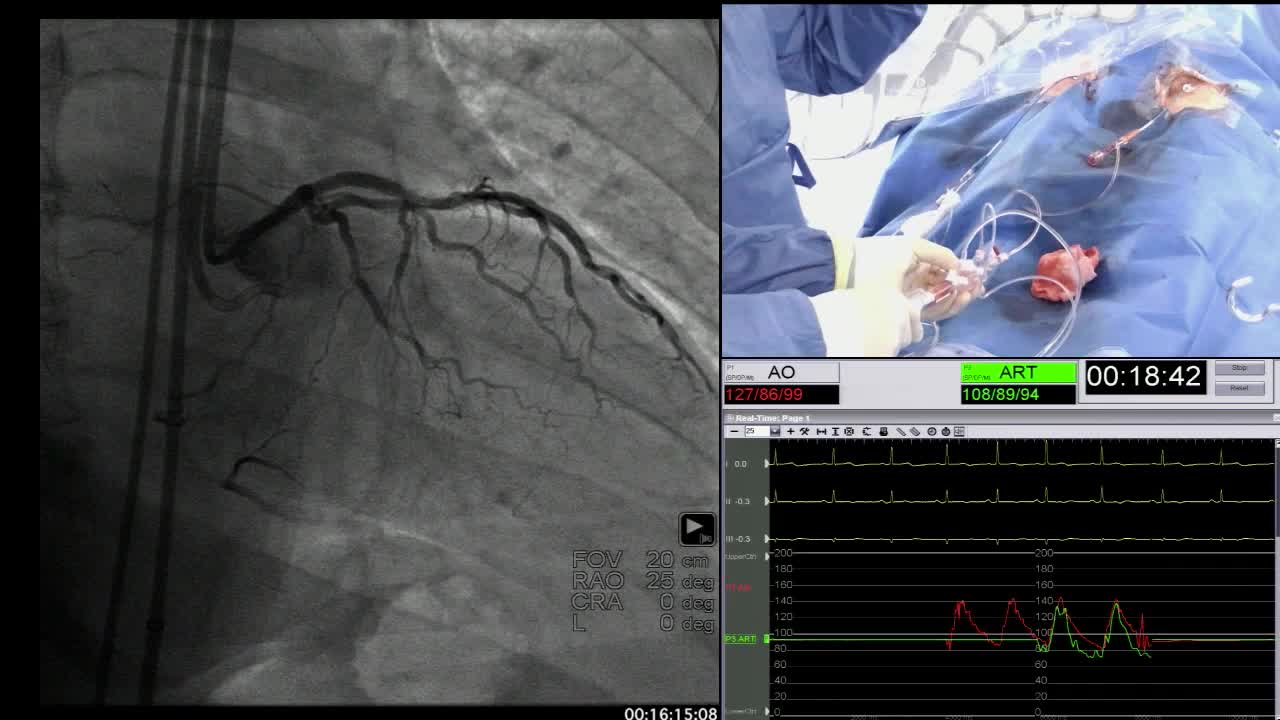

Proximal cap troubleshooting - shifting targets and side branches